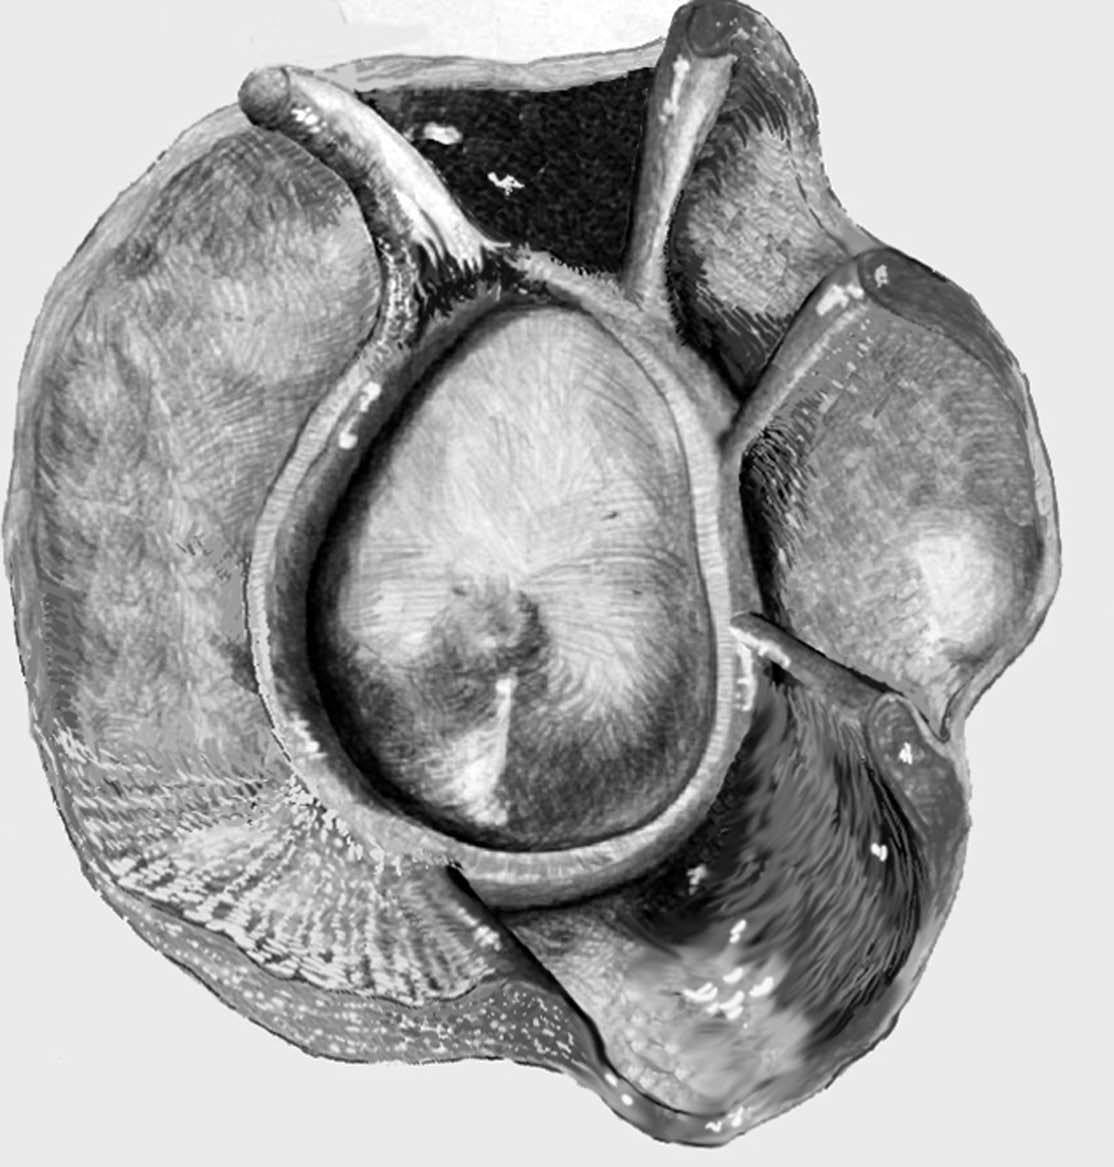

ALPSA (anterior labroliamentous periosteal avulsion)

Al igual que en el apartado anterior, existe también una separación de LG junto con la cápsula y el periostio, pero a diferencia de las lesiones de Bankart o Perthes, el LG se desplaza hacia dentro, por detrás del borde de la glenoides18 (fig. 12). La lesión de ALPSA puede cicatrizar por sinovialización (fig. 12), pero continúa siendo de carácter inestable.

Fig. 12.--ALPSA (anterior labroliamentous periosteal avulsion) agudo (A) y crónico (B). Nótese la separación del labio glenoideo y su desplazamiento posterior y medial por detrás del reborde glenoideo (flecha en A). En una fase crónica el labio glenoideo no se distingue como una estructura separada, sino como un engrosamiento de la unión entre el labio, la cápsula y el periostio (flecha en B).